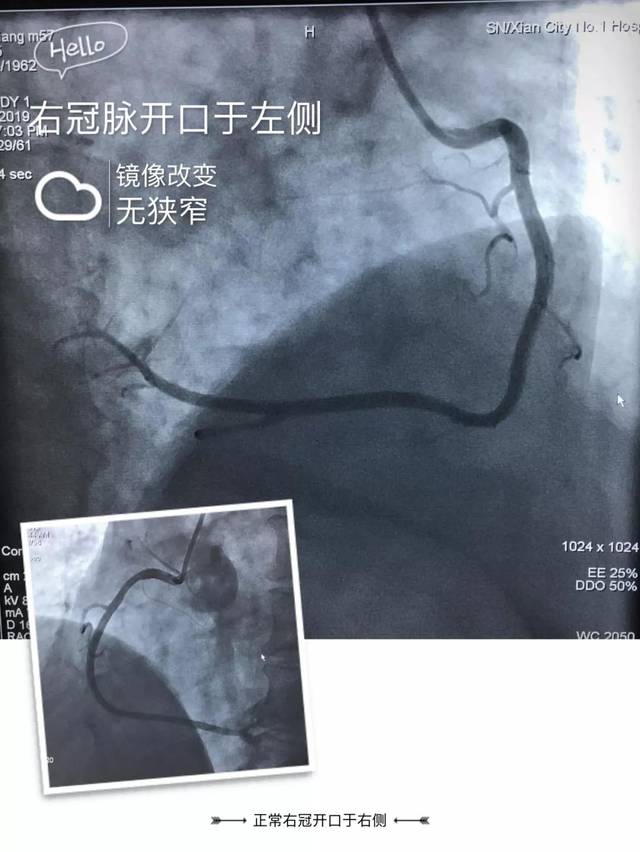

硬实力第一医院首例右位心冠脉造影顺利完成